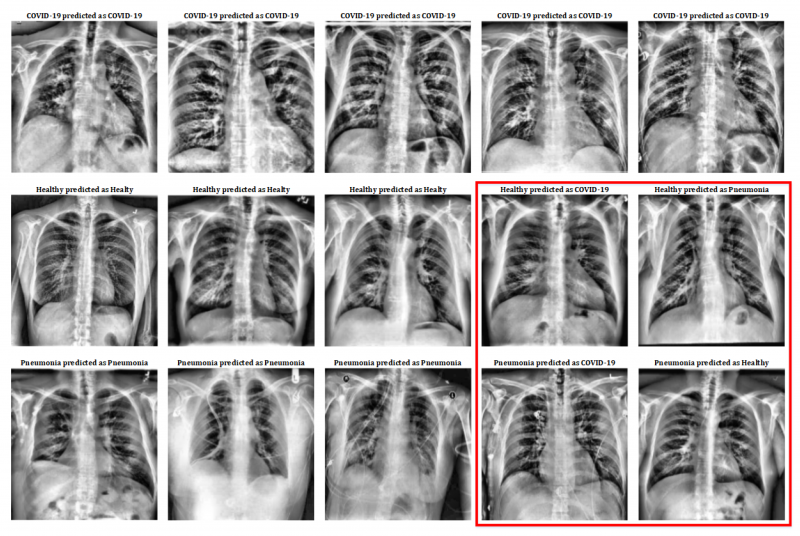

Pre-processing results. Image courtesy of Applied Sciences.

Similarly, this work analyses the effectiveness of a deep learning model based on a VGG-16 neural network for the identification of pneumonia and COVID-19 using X-rays of the torso. The results, published in the journal Applied Sciences, reveal that this method is around 100% effective in the identification of COVID-19, proving that it can be used as an aid to diagnose this disease.